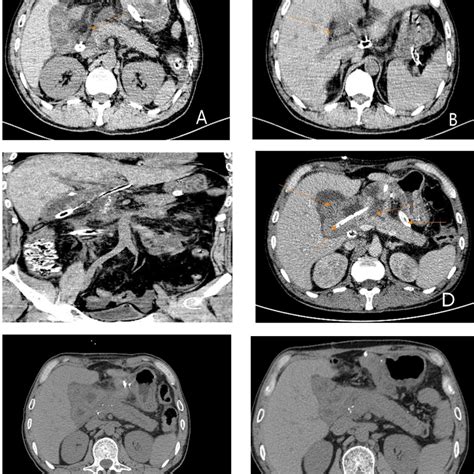

Hey guys, let’s dive into the world of medical imaging, specifically focusing on the abdomen CT scan . If you’ve ever had or are about to have one, you probably want to know what’s going on, right? Well, you’ve come to the right place. A CT scan, or computed tomography scan, is a powerful diagnostic tool that uses X-rays to create detailed cross-sectional images of your body. When we talk about an abdomen CT scan , we’re specifically looking at the organs and structures within your abdominal cavity. This includes vital parts like your liver, kidneys, spleen, pancreas, intestines, stomach, and even major blood vessels. It’s like having a super-detailed, 3D look inside your belly without needing to go in with a scalpel. Doctors use it to spot a whole range of issues, from infections and inflammation to tumors and injuries. The technology behind it is pretty neat – essentially, the CT scanner takes multiple X-ray images from different angles, and a computer then pieces them together to form incredibly precise slices of your abdomen. This allows for early detection and accurate diagnosis, which, as we all know, is super important for getting the right treatment plan in place. So, when your doctor suggests an abdomen CT scan , it’s because they need a clearer picture of what might be causing your symptoms, or to monitor a known condition. It’s a non-invasive procedure that provides a wealth of information, making it a cornerstone of modern diagnostic medicine. We’ll be breaking down what it involves, why it’s done, and what you can expect, so stick around!

So, why exactly would your doctor recommend an abdomen CT scan ? There are a ton of reasons, but they generally boil down to needing a closer look at what’s happening internally. One of the most common uses is to investigate abdominal pain . If you’ve got persistent or severe pain in your belly, a CT can help pinpoint the cause, whether it’s appendicitis, kidney stones, gallstones, diverticulitis, or something else entirely. It’s a fantastic tool for spotting these kinds of acute conditions quickly. Beyond just pain, CT scans are crucial for diagnosing and staging cancer . They can detect tumors in abdominal organs like the liver, pancreas, or colon, and help determine if the cancer has spread to other areas. This information is absolutely vital for planning the best course of treatment, whether that involves surgery, chemotherapy, or radiation. We also use abdomen CT scans to look for signs of infection or inflammation . Conditions like abscesses (collections of pus) or inflammatory bowel disease (like Crohn’s disease or ulcerative colitis) can often be visualized on a CT scan. If you’ve had an injury to the abdomen, a CT scan is often the go-to imaging method to check for internal bleeding or damage to organs. This is especially important in trauma situations where time is critical. Furthermore, doctors use CT scans to monitor the effectiveness of treatments for various abdominal conditions or to check for recurrence of disease after treatment. It’s also used to guide biopsies, where a small sample of tissue is taken from an organ for examination. So, as you can see, the abdomen CT scan is a versatile and indispensable tool in a doctor’s arsenal for a wide range of diagnostic and monitoring purposes. It gives them the detailed insights they need to make informed decisions about your health.